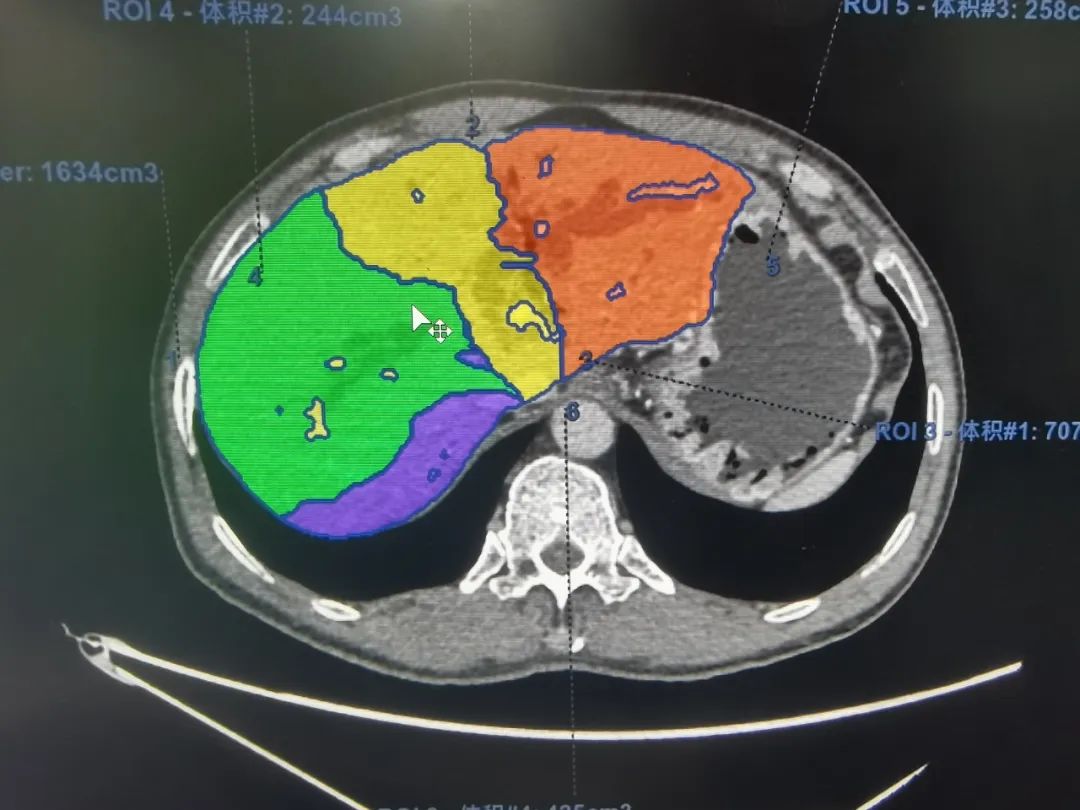

▲影像科供图

基于术前影像,结合肿瘤实际累及程度、解剖变异以及切离极限点,外科团队邀请多科室开展MDT讨论,规划个体化精准手术方案。充分术前准备后,为其行“肝门部胆管癌根治术”。主刀手沉着冷静,仔细探查,精准分离,清扫组织,以雷霆之势完整切除病灶。“清点器械纱布,确认无误,关腹。”手术顺利,经过术后严格管理和精心护理,宗师傅很快康复出院,对东方医院集团广济医院普外科团队精湛的技术赞不绝口。